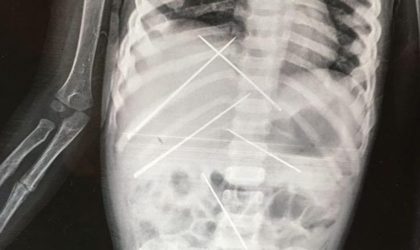

Φρίκη: Γεμάτο βελόνες το κορμάκι 3χρονης από μαύρη μαγεία

Στην περιοχή Μπανκούρα, στην Ινδία Βρίσκονταν μέσα της για τουλάχιστον 15-20 ημέρες, ενώ είχε και σπασμένο χέρι – Σοκ στους...